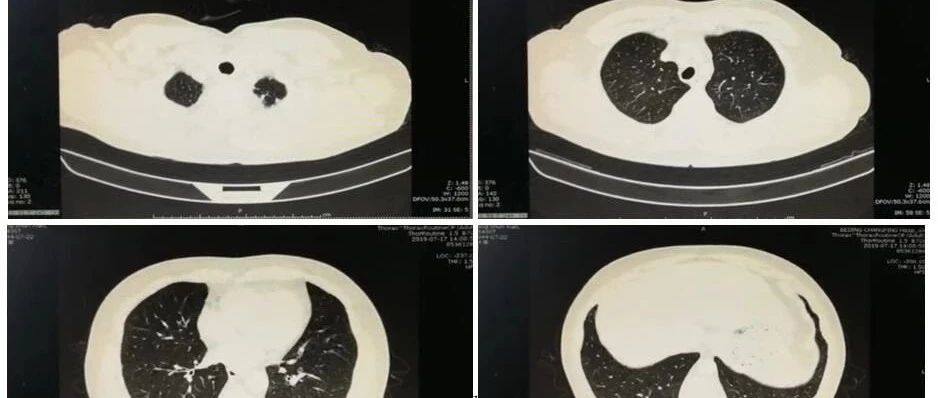

最后青年患者,肿瘤标记物CA199异常升高,通过文献回顾了解与肺隔离症关系,对临床发现感染相关疾病伴CA199升高提供了更好的分析思路。肺炎精粹2019-12-10 16:57 郭文佳、牟向东 -